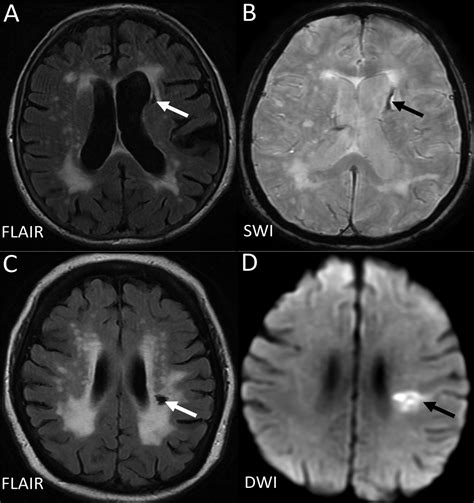

Diagnosing Chronic Microvascular Ischemic Changes

Diagnosing chronic microvascular ischemic changes involves a combination of medical history, physical examination, and diagnostic tests. Some of the common diagnostic methods include:

• Imaging Tests: Such as ultrasound, CT scans, and MRI to visualize the blood vessels and assess blood flow.